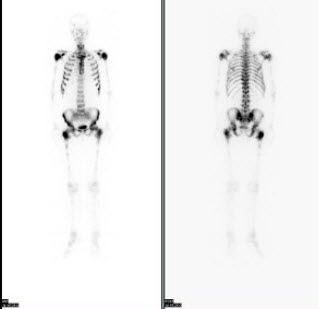

41、多项选择题

男,21岁,临床诊断胃癌,诉全身多处骨关节疼痛,行全身骨显像如图,对此影像下列描述正确的是()

A.胸12椎体放射性“冷区”

B.若同时X线检查为阴性则提示骨转移可能性大

C.“冷区”的出现一定表明骨转移

D.患者胸骨浓聚提示骨转移

E.胸12椎体可能存在肿瘤的骨髓浸润

点击查看答案